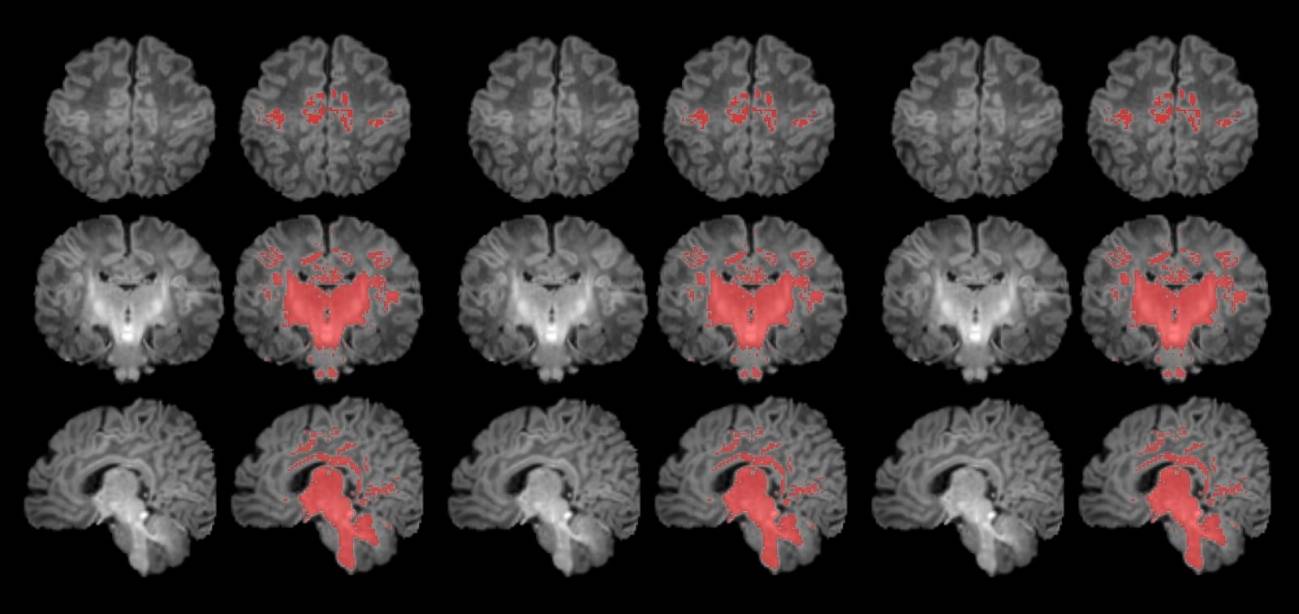

Es el primer estudio que mide con resonancia magnética la mielinización cerebral de los recién nacidos. / Pujol et al., 2025 | ISGlobal

Para llevar a cabo el estudio se reclutó a mujeres embarazadas en seguimiento en el Hospital Clínic Barcelona, el Hospital de Sant Pau y el Hospital Sant Joan de Déu. Se monitorizaron los niveles de contaminantes atmosféricos a los cuales estaban expuestos durante la gestación y, después del parto, se seleccionó a 132 recién nacidos. A estos se les realizó una resonancia magnética antes de cumplir el primer mes de vida para observar el grado de maduración cerebral según sus niveles de mielinización.

Los resultados muestran una correlación clara entre una mayor exposición materna a PM2.5 durante el embarazo y una menor mielinización en el cerebro de los recién nacidos.